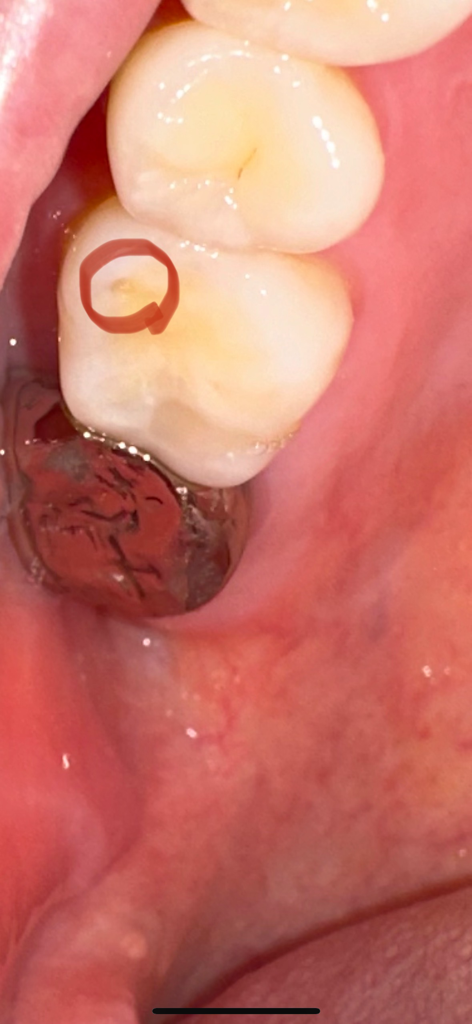

저부분은 충치나 다른 이유떄문에 생긴거 같진 않고 치아가 교모되서 생긴거 같습니다. 레진으로 치료 하셔도 교합조정하면 다 삭제를 해야될꺼 같아요

해당 부위는 치아에 과도한 힘으로 인해서 마모증으로 인해서 깨져 나간 부위입니다.

치아가 너무 과하게 힘을 받았을 경우에 생기는 증상인데 해당 부위를 레진으로 메꾼다고 해도 다시 힘이 가해지면 탈락해야 되기 때문에 해당 부위를 충전한다기보다 해당 부위에 가해지는 힘을 줄일 수 있도록 노력을 하는 것이 좋습니다.

약간의 마모와 파절이 있는 것 같습니다. 다만, 사용하는데는 큰 문제가 없고 오히려 레진 등의 재료로 떼우고자 하면 정상 부위도 조금 갈아내야 하기 때문에 굳이 그런 치료를 진행하진 않은 것 같고 날카로운 부분만 조금 다듬어 준 것 같습니다. 해당 부위가 신경쓰이거나 음식물이 자주 끼거나 한다면 레진 등으로 떼우는 치료를 고려해봐도 좋을 것 같습니다.